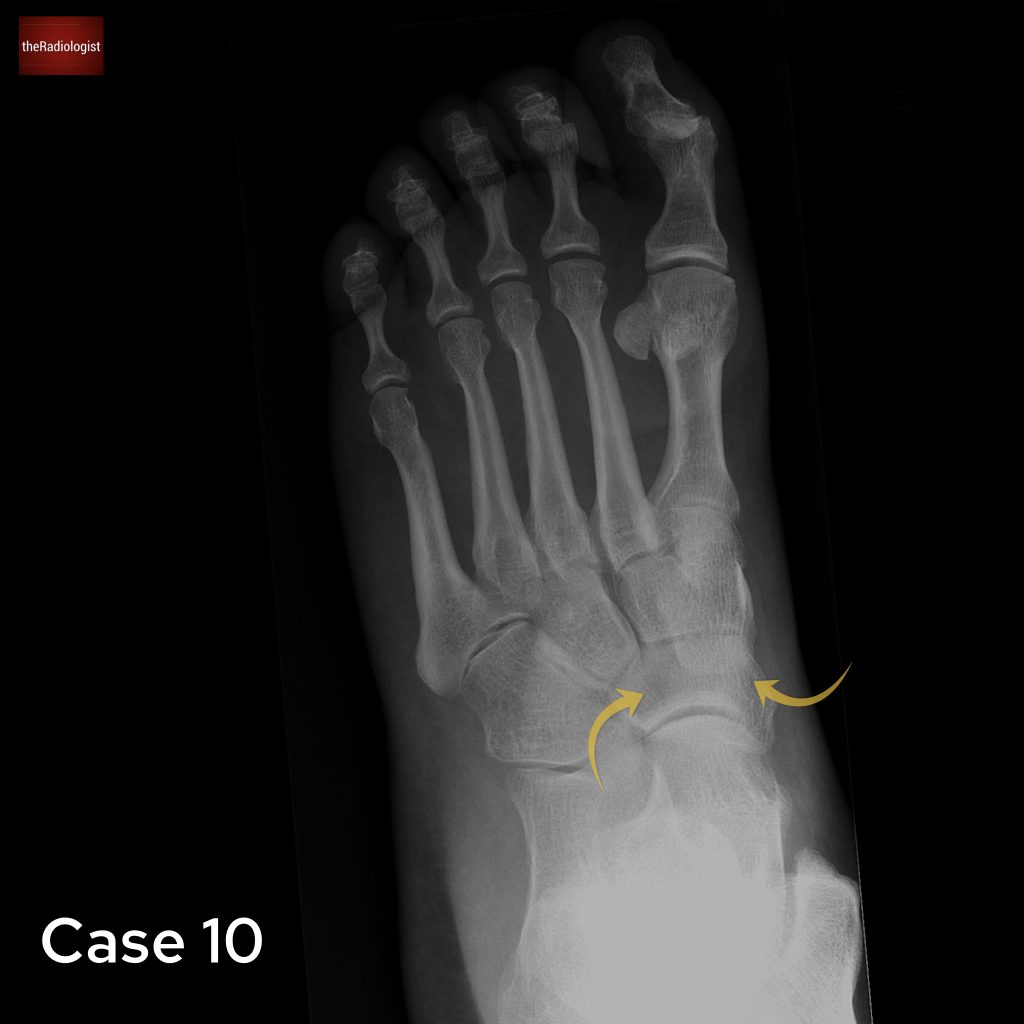

Case 10

For the last case let’s look at a foot X-Ray. What are the arrows pointing at?

Choose from one of the following options: